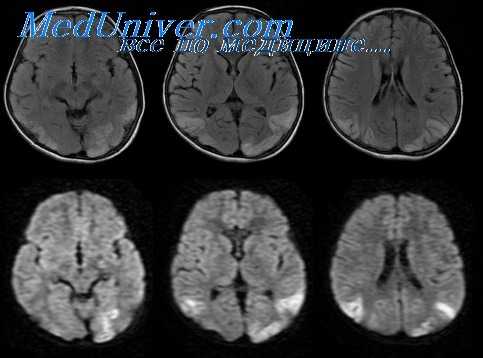

Цереброваскулярный сифилис характеризуется выраженным воспалением мозговых оболочек и кровеносных, сосудов, которое приводит к развитию инфарктов мозга, преимущественно в тонах кровоснабжения артерий среднею калибра. Инсультам предшествуют продромальные симптомы, такие как головная боль, изменения личности, головокружение, нарушения сна и другие неспецифические проявления. КТ и МГГ выявляют зоны инфарктов, ангиофафическос исследование — сужение артерий среднего калибра Изменения ЦСЖ соответствуют хроническому воспалительному процессу.

Наиболее безопасным и эффективным способом, позволяющим диагностировать опухоль спинного мозга, выступает МРТ позвоночника. Метод дает возможность послойно визуализировать расположенные в позвоночном столбе мягкотканные образования, проанализировать объем и распространенность опухоли, ее локализацию по отношению к веществу, оболочкам и корешкам спинного мозга, сделать предварительную оценку гистоструктуры новообразования.

Наиболее информативным методом исследования является МРТ позвоночника, позволяющая оценить локализацию и размер злокачественной опухоли спинного мозга, ее отношение к различным мягкотканным и костным структурам. При недоступности МРТ пациента направляют на контрастную миелографию, при помощи которой можно определить тип (экстрамедуллярная или интрамедуллярная) и уровень расположения опухоли. Пневмомиелографию и изотопную миелографию в настоящее время почти не применяют из-за высокого риска развития осложнений. Диагноз подтверждают на основании результатов гистологического исследования образцов новообразования, полученных во время хирургического вмешательства.